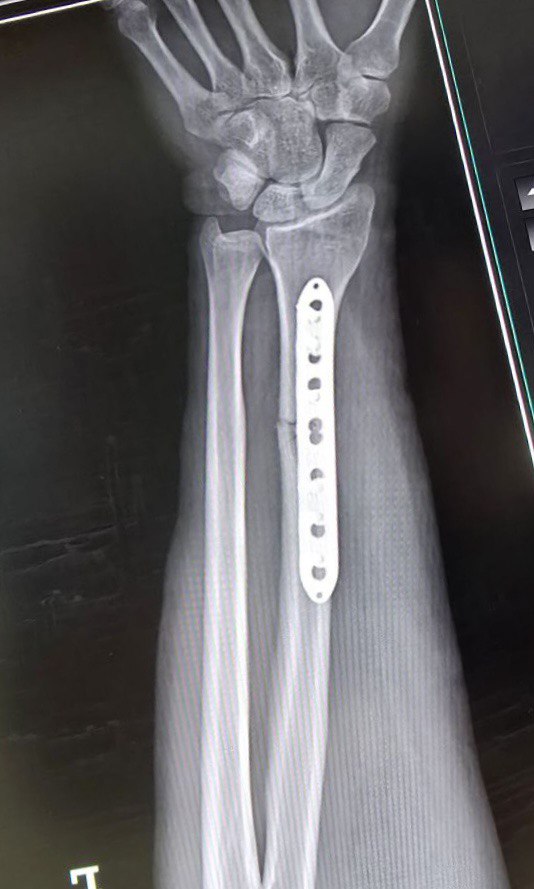

Клинический случай: перелом диафиза лучевой кости

Клинический случай с повреждением диафиза лучевой кости и последовательным контролем состояния.